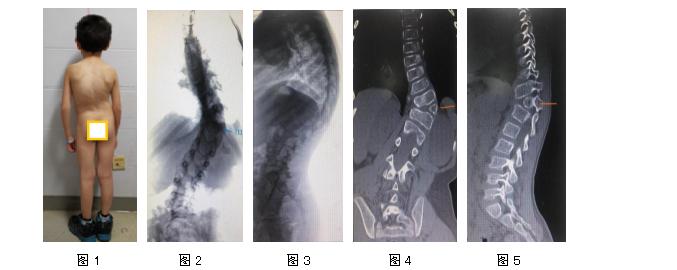

小明(化名)是一位7岁的男孩儿,当他还在襁褓中时,细心的家长就发现孩子脊柱侧凸,起初没有太在意,可是随着孩子渐渐长大,这个问题逐年在加重,家长坐不住了,赶紧带着孩子辗转全国多家三甲级医院求治,7年下来,都没有达到理想效果,家长心急如焚,最终来到我院。体格检查:身高116cm,双肩不等高,剃刀背,胸腰椎左侧凸,胸椎代偿性右侧凸,下肢感觉、运动、反射检查正常。影像学提示胸腰椎左侧凸,胸11左侧半椎体。T10-T12Cobb角正位90°,T1-T12侧位88°,就是说孩子脊柱侧弯非常严重,弯曲度达到90度了。胸椎MR提示:胸11节段脊髓因脊椎侧凸旋转滑移至椎管右侧,受压明显。如此严重的侧弯必须要进行手术矫正!

图1为患者术前观 图2-7为术前影像学